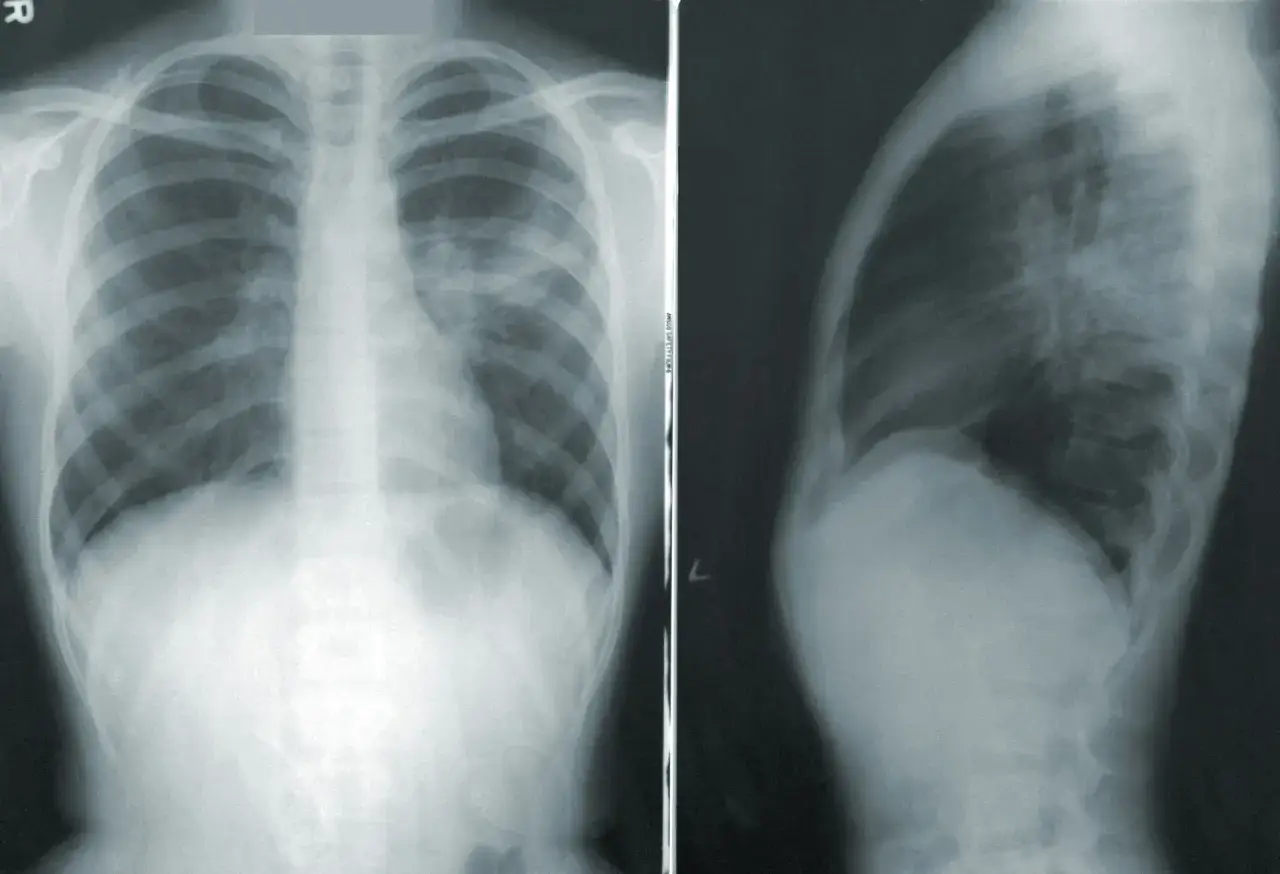

RTG klatki piersiowej: Złoty standard w rozpoznawaniu odmy

Po wstępnym badaniu fizykalnym, zdjęcie rentgenowskie (RTG) klatki piersiowej jest podstawowym i najczęściej wystarczającym badaniem do potwierdzenia odmy płucnej. Jest to szybka, łatwo dostępna i nieinwazyjna metoda. Na zdjęciu RTG lekarz może wyraźnie zobaczyć:

- Obecność powietrza w jamie opłucnej: Powietrze na RTG jest widoczne jako ciemna przestrzeń bez rysunku płucnego.

- Zapadnięte płuco: Brzeg zapadniętego płuca jest widoczny jako cienka linia, oddzielająca płuco od zgromadzonego powietrza.

- Przemieszczenie śródpiersia: W przypadku dużej odmy, zwłaszcza prężnej, widoczne może być przesunięcie serca i tchawicy na stronę przeciwną do odmy.